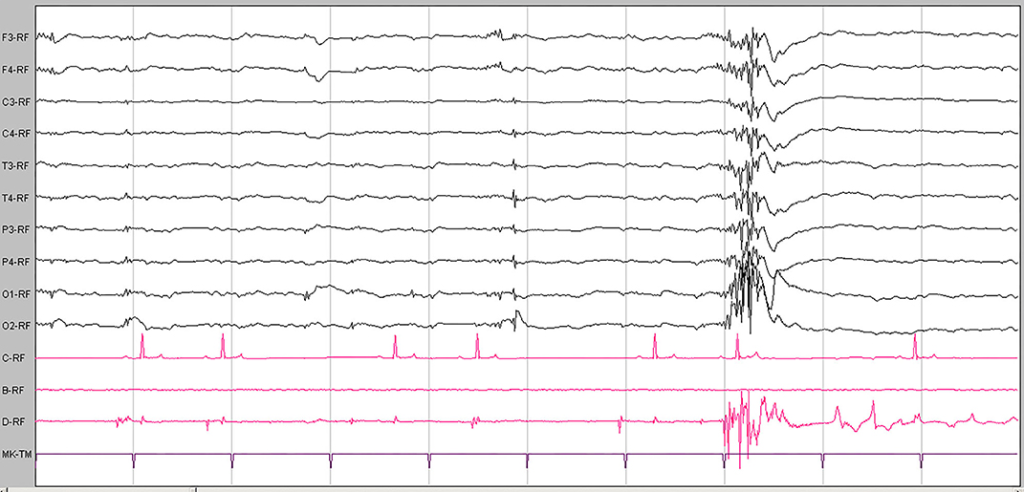

EEG: Diffüz spike–wave****, Fotosensitivite